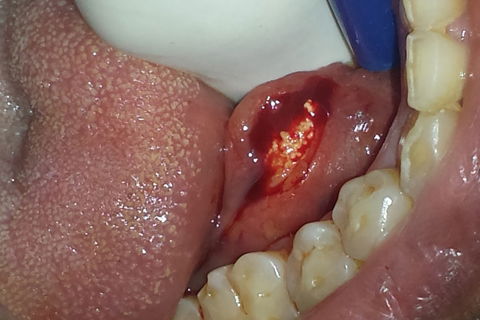

Incisão do ducto da glândula e exposição do Sialolíto

Paciente do sexo masculino com queixa de aumento de volume em assoalho bucal ha 3 meses.Ao exame clínico , presença de nódulo endurecido em região paramediana direita do assoalho de boca, endurecido e rugoso, com coloração da mucosa que o recobria. Imagem da radiografia panorâmica evidencia imagem radiopaca de formato alongado ( formato semelhante a dente) se sobrepondo às coroas dos dentes inferiores anteriores.Realizada radiografia oclusal inferior, evidenciando imagem radiopaca em tecidos moles da região sublingual direita compatível com sialolito (formato de dente canino).Realizada incisão sob anestesia local infiltrativa em assoalho de boca, com posterior divulsão e incisão no ducto da glândula submandibular direita, observando-se sialíto de grandes dimensões,o qual foi removido. Sutura e pós operatório satisfatório sem intercorrências.